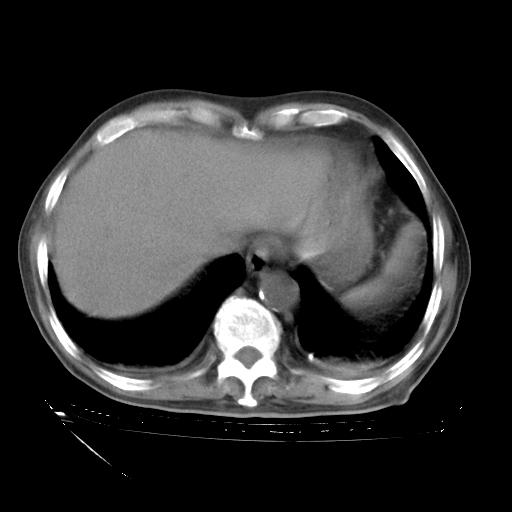

甲强龙80mg/日+抗结核治疗(异烟肼+利福霉素+乙胺丁醇)10天。复查肺部CT。

治疗10天肺部CT